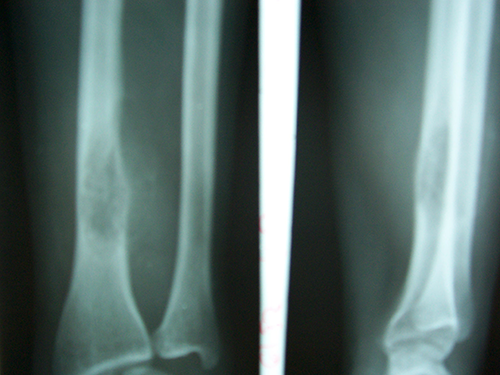

Case:3 Ewings Tibia

Spine Best doctor in satellite|Best Orthopedic Surgeon

Pre-Op

Spine Treatment In Jaipur|Sports Injuries Doctor

Post-Op